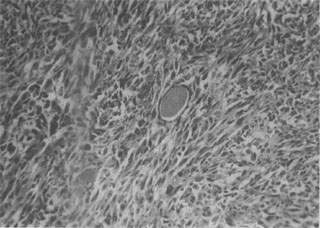

3.脂肪内(liposarcoma) 为肉中较常见的一种类型,多发生于大腿及腹膜后的软组织深部。来自原始间叶组织,极少从皮下脂肪层发生,与脂肪的分布相反。这说明脂肪肉极少是由脂肪恶变而来,而是一开始即具恶性特征。本多见于40岁以上成人,极少见于青少年。肉眼观,大多数肿呈结节状或分叶状,表面常有一层假包膜,可似一般的脂肪,亦可呈粘液性外观,或均匀一致呈鱼肉样。本细胞形态多种多样,可见分化差的星形、梭形、小圆形或呈明显异型性和多形性的脂肪母细胞,胞浆内可见多少和大小不等的脂滴空泡(图7-18),也可见分化成熟的脂肪细胞,并常以某种细胞成分为主。间质有明显粘液性和大量血管网形成者,称为粘液样型脂肪肉。当以分化差的小圆形脂肪母细胞为主(圆形细胞型脂肪肉)或以多形性脂肪母细胞为主时(多形性脂肪肉),恶性程度高,易有复发和转移。

图7-18 脂肪肉

细胞分散,胞浆内含大小不等的脂肪空泡。细胞间有多量粘液性基质(图中呈灰色),并见巨细胞(插入图)